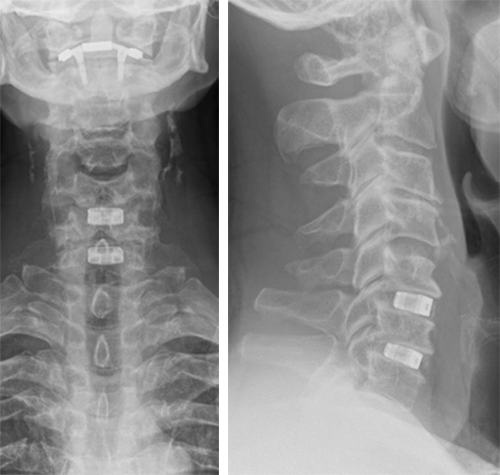

The patient underwent anterior decompression and fusion C5-6-7 with Conduit stand-alone cages C5-6-7. Restoration of lordosis C5-7 (Fig 7).

Follow-up at 3 months

The patient had an uneventful recovery, with neither neck nor arm pain, but with good residual range of motion. He had persistent loss of sensation C6 dermatome L.